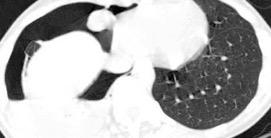

Tromboembolismo pulmonar.

Frecuencia del derrame:

Rx: 32%. TC: 47%

Unilateral. 85%

< 1/3 del hemitórax: 90%

Todos exudados

58% con eritrocitos

21% tabicación lo que causa demora en el diagnóstico

TEP. Empiema pleural. Atelectasia redonda

Porcel JM et al. Analysis of pleural effusions in acute pulmonary embolism: radiological and pleural fluid data from 230 patients. Respirology 2007/ Iguchi T et al. Desquamation of the subpleural lung parenchyma caused by empyema after pulmonary embolism: A case report. Respirol Case Rep. 2022 .

Derrame pleural 43-48% de pacientes con embolismo.

< 1/3 de hemitórax: 90%.(puede haber en lado opuesto).

Siempre exudados.

75% de los pacientes con TEP y derrame pleural tienen dolor pleurítico.

La disnea desproporcionada